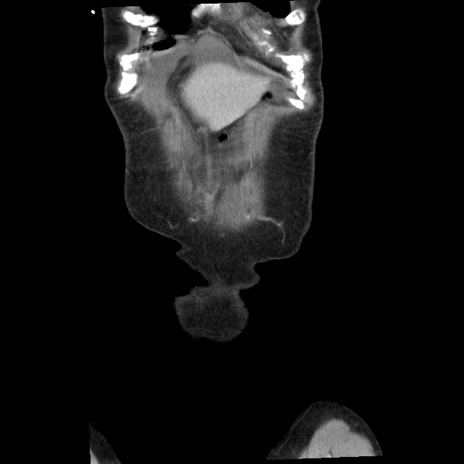

矢状断像